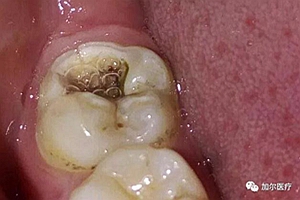

一張開嘴大牙上都有黑線,難看是一回事就怕牙齒會爛掉,可是牙醫(yī)檢查完說不用補牙,難道記錯了,莫非是洗牙,既然蛀牙前期是黑線,那干嘛不補?奇怪的是,為什么別人的黑線可以直接補牙?

因為這得看牙齒黑線被齲壞的程度,說明已經(jīng)開始蛀牙,但不是洗牙就能洗掉,細小黑線一般牙醫(yī)不給補,得等到黑線變粗,不然鉆完黑色腐敗物補了容易脫落,雖然你早晚刷牙清潔到位,不過隱蔽位置難免有殘渣殘留在大牙咬

合面,不容易清理,細菌腐蝕牙釉質(zhì)形成黑色產(chǎn)物,所以大牙才長有黑線。